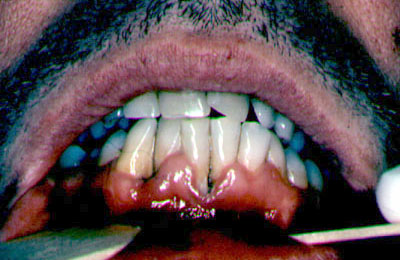

Periodontitis

ulceronecrotizante |

La

periodontitis ulceronecrotizante se manifiesta en menos

del 5% de los casos con pérdida de hueso y tejido blando en los

pacientes VIH con recuento de CD4 inferior a 200 y puede progresar a

estomatitis ulceronecrotizante Se encuentran microorganismos usuales